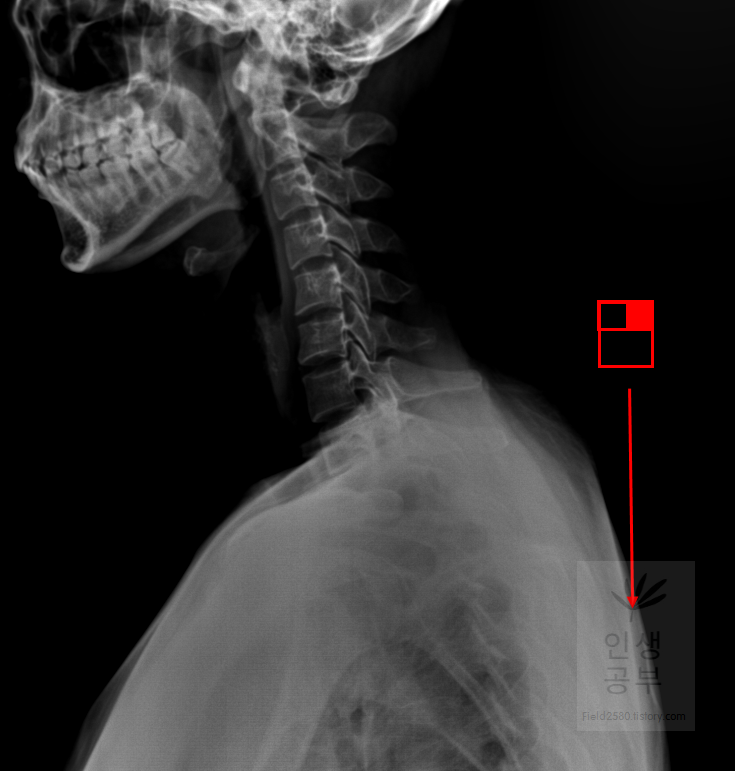

빨간색 네모칸으로 쳐진 대각선으로 그어진 줄 모양이 선을 긋거나 거리를 측정할 때 사용하는 버튼입니다.

돋보기 화면이 있는데 확대 축소하는 방법에 대해서 알아보겠습니다. 화면 전체를 확대하거나 축소할 때는 도구모음에 돋보기 화면에 ±가 있는 버튼을 눌러줍니다. 빨간색 네모상자 안에 있는 버튼이 확대하거나 축소할 때 사용하는 버튼입니다. 부분적인 부분만 확대해서 보고 싶을 때는 매직 글래스라는 메뉴를 이용해서 부분적인 확대를 할 수 있습니다. 먼저 화면 전체를 확대하거나 축소할 대 쓰는 도구모음 버튼을 어떻게 사용하는지에 대해서 알아보겠습니다.